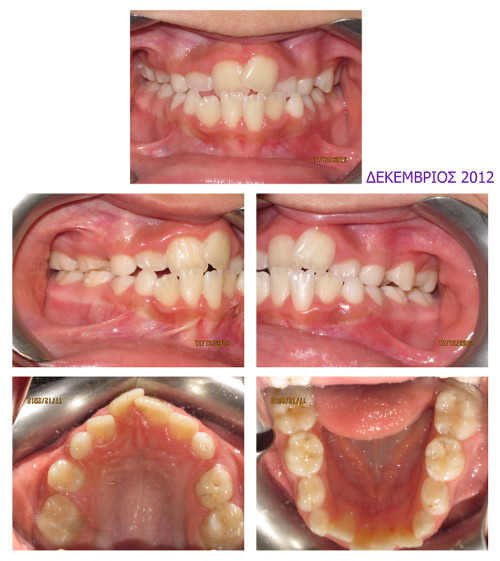

Συνωστισμός και ψευδοπρογναθισμός

Αρχικό Στάδιο